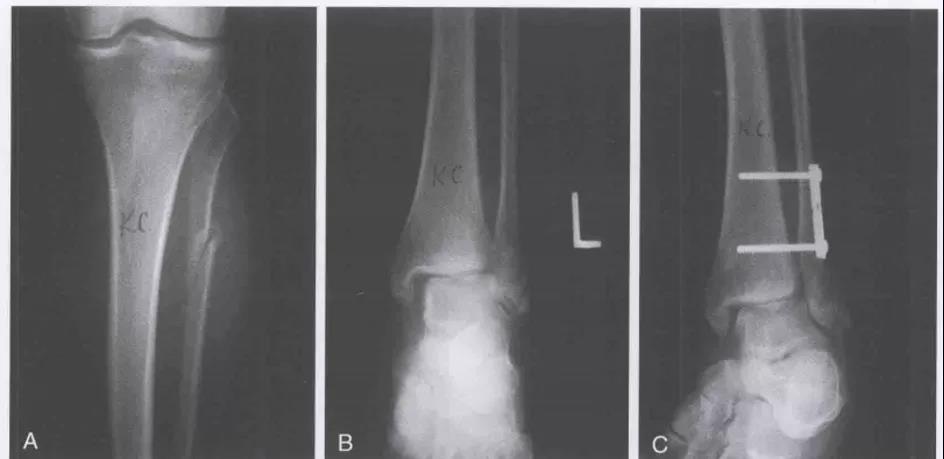

Lauge-Hansen-旋前外旋(PE)受伤时,足处于旋前背伸外展位,距骨外旋。Ⅰ:三角韧带紧张,造成三角韧带损伤或者是内踝撕脱性骨折。Ⅱ°:外力继续作用,距骨外旋造成下胫腓前韧带和骨间韧带损伤,或者韧带附着点撕脱性骨折。Ⅲ°:外力继续作用,腓骨受到向外向后的旋转应力,造成腓骨的螺旋性骨折(特点:腓骨由于足本身的位置,外旋力大,向上传导,骨折位于下联合上方,甚至可以达到腓骨颈部位- Maisonneuve骨折)。Ⅳ:外力继续作用,下胫腓后韧带紧张,造成下胫腓后韧带断裂或后踝撕脱骨折。